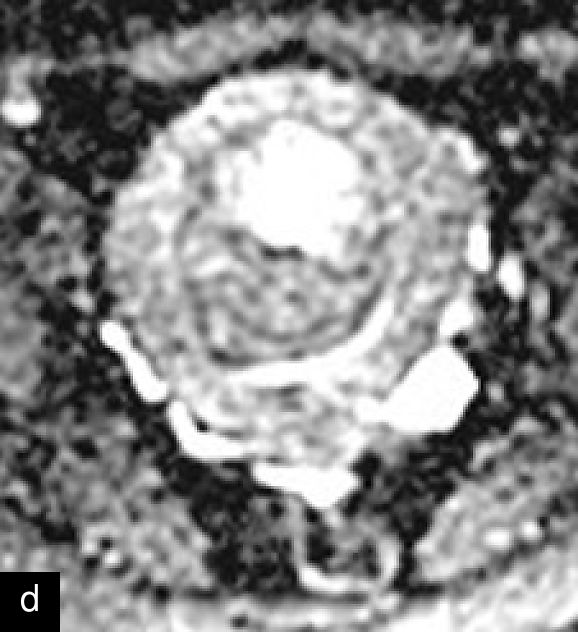

Magnetic resonance imaging (MRI) may help in the preoperative evaluation of uterine masses, when ultrasound findings are inconclusive. MRI offers higher accuracy in soft-tissue contrast, a larger field of view, diffusion imaging and multiplanar capabilities.15 A recent consensus statement has provided a standardized approach to MRI assessment, emphasizing its role in distinguishing uterine sarcomas/STUMP from benign leiomyomas.15 Features suggestive of malignancy include irregular margins; heterogeneous and high signal on T2 weighted imaging; and hemorrhagic and necrotic changes, with central non-enhancement, hyperintensity on diffusion-weighted imaging (DWI), and low values for apparent diffusion coefficient (ADC)15,25,39,40,41 (Figure 7). Diagnostic algorithms have been proposed to support MRI interpretation in differentiating between benign and malignant uterine lesions, and recent studies have explored the use of artificial intelligence to further enhance diagnostic accuracy.42,43,44 Emerging technologies, including radiomics and machine learning, show promise in improving diagnostic precision, although standardization and external validation remain essential.39,45

7

Magnetic resonance imaging (MRI) of a STUMP. (a) Contrast-enhanced MRI showing heterogeneous enhancement of the mass. (b) T2-weighted MRI demonstrating a hyperintense lesion with heterogeneous signal intensity. (c) Diffusion-weighted imaging (DWI) highlighting areas of restricted diffusion. (d) Apparent diffusion coefficient (ADC) map, showing low ADC values suggestive of increased cellularity, aiding in the differentiation of STUMP from benign leiomyomas and malignant leiomyosarcomas.